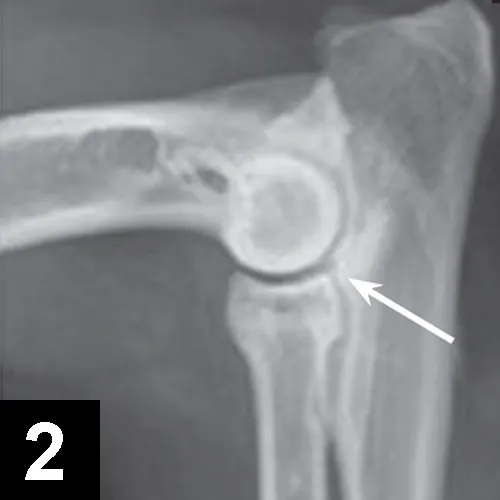

• Orthogonal radiographs may confirm diagnosis, especially with OCD lesions (Figures 1 and 2).

X-ray of a dog’s elbow with arrows pointing to lesions.

FIGURE 1

Craniocaudal view of an elbow with OCD lesion (arrow).